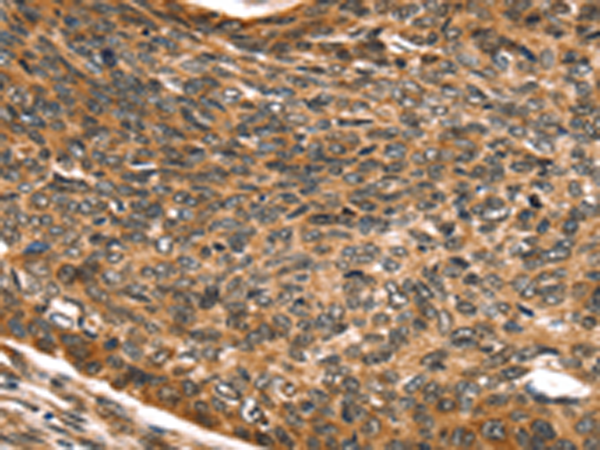

分类: 科研抗体货号: P01830别名: Mvp1应用: WB,IHC反应种属: Human, Mouse

分类: 科研抗体货号: P01824别名: SNO; SnoA; SnoI; SnoN应用: WB,IHC反应种属: Human, Mouse

分类: 科研抗体货号: P01821别名: SNAP-23; SNAP23A; SNAP23B; HsT17016应用: WB,IHC反应种属: Human, Mouse, Rat

分类: 科研抗体货号: P01882别名: TCFEB; BHLHE35; ALPHATFEB应用: WB反应种属: Human, Mouse

分类: 科研抗体货号: P01906别名: CC3; TIP30; SDR44U1应用: WB反应种属: Human, Mouse

分类: 科研抗体货号: P01874别名: EBI; TBL1; SMAP55应用: WB,IHC反应种属: Human, Mouse

分类: 科研抗体货号: P01903别名: RNF9; HERF1; RFB30应用: WB,IHC反应种属: Human

分类: 科研抗体货号: P01868别名: TAF2I; PRO2134; TAFII28; MGC:15243应用: WB,IHC反应种属: Human, Mouse, Rat

分类: 科研抗体货号: P01898别名: AFP; RNF95; ZNF173应用: WB,IHC反应种属: Human, Mouse, Rat

分类: 科研抗体货号: P01859别名: slp5应用: IHC反应种属: Human, Mouse, Rat